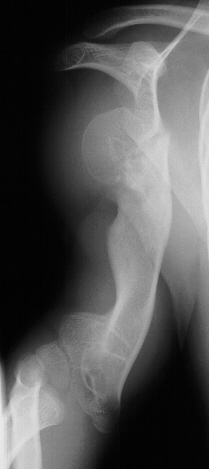

deformity of the metaphyseal region. By age 11 the child had a

good gait pattern however the upper extremity length discrepancy

was becoming a cosmetic and functional concern. X-rays at age

11 show significant angulation developed in the humerus(image

3,4 & 5). However tibial growth was good .